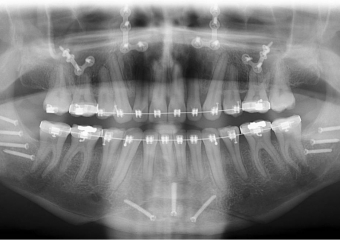

Raio x inicial